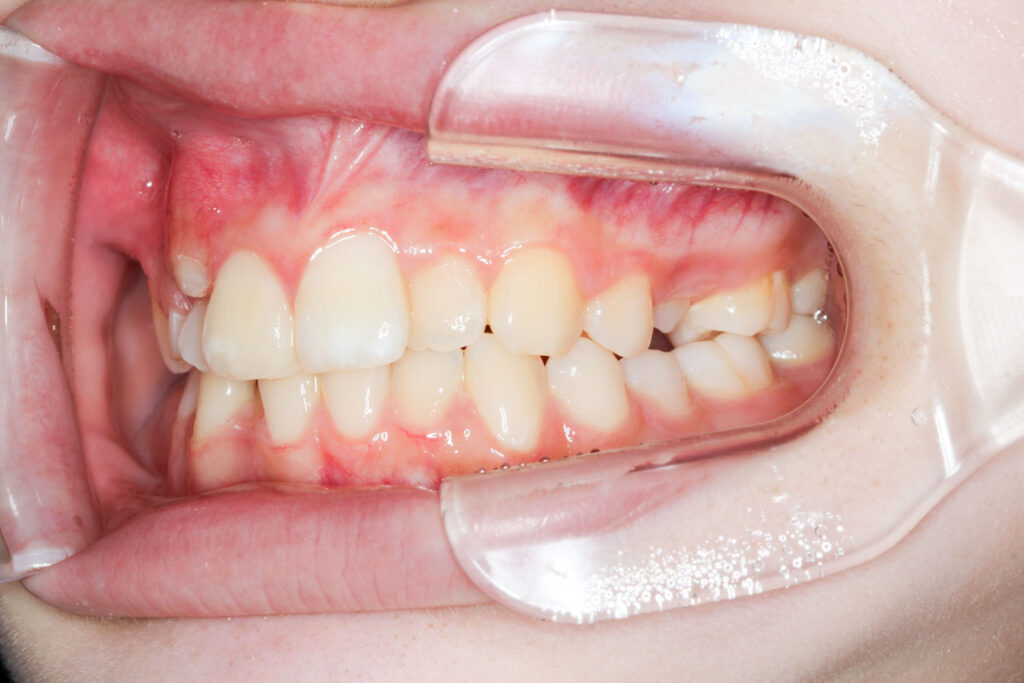

Before

After

年齢 10代

治療装置 上は裏側の矯正装置(フルリンガル)

治療内容 非抜歯

治療期間 2年8か月

リスク 歯の移動に伴う痛み、歯肉退縮、歯根吸収、歯肉炎、虫歯

主訴 ガタガタと隙間が気になる

症状 叢生と正中離開

治療回数 36回程度

総額費用 140万円程度